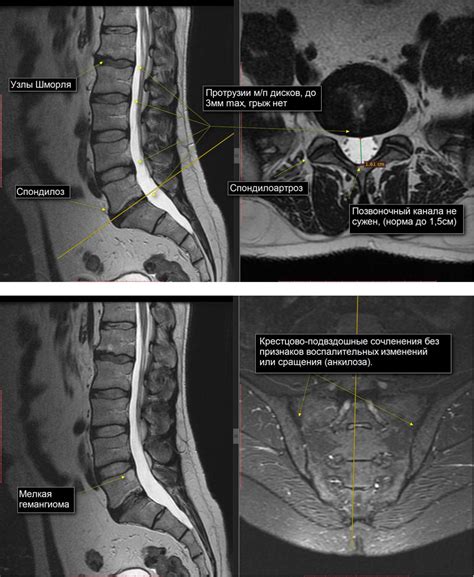

- Магнитно-резонансная томография (МРТ) – использует сильные магнитные поля и радиоволны для создания подробных 3D изображений позвоночника. Позволяет выявить структурные изменения, воспалительные процессы, состояние мягких тканей.